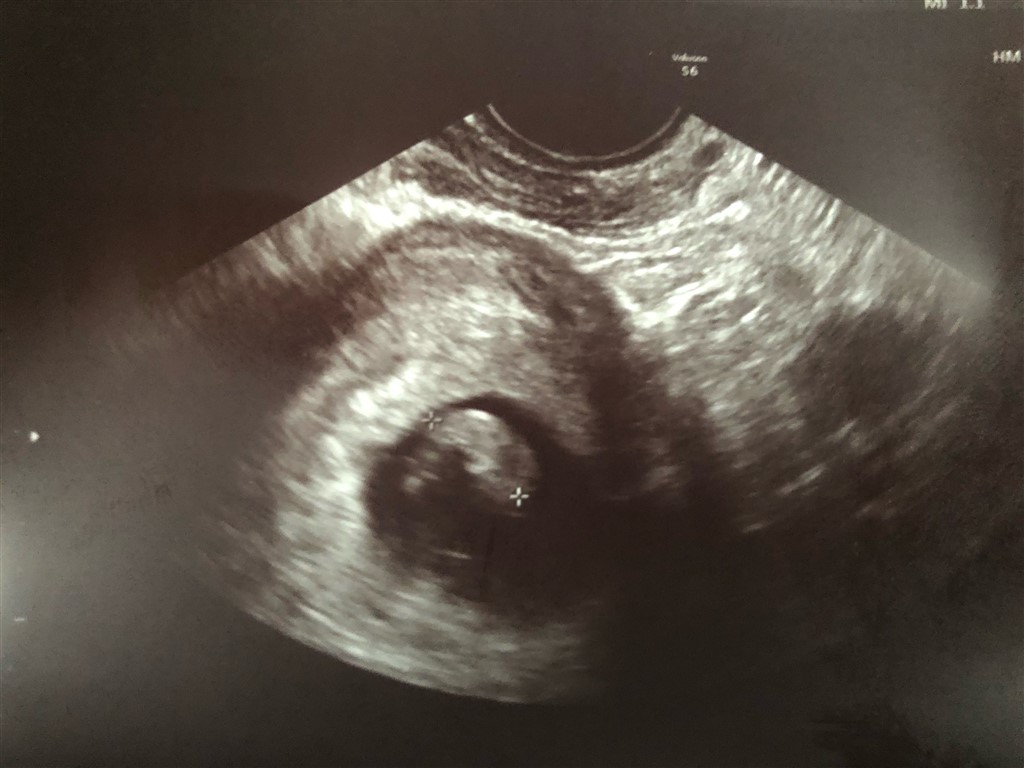

Er 7+5 og i dag har vi set den lille reje som var perfekt i målene i forhold til graviditetsuge og med et blinkende hjerte

Vedhæftede fotos (klik for at se i fuld størrelse)